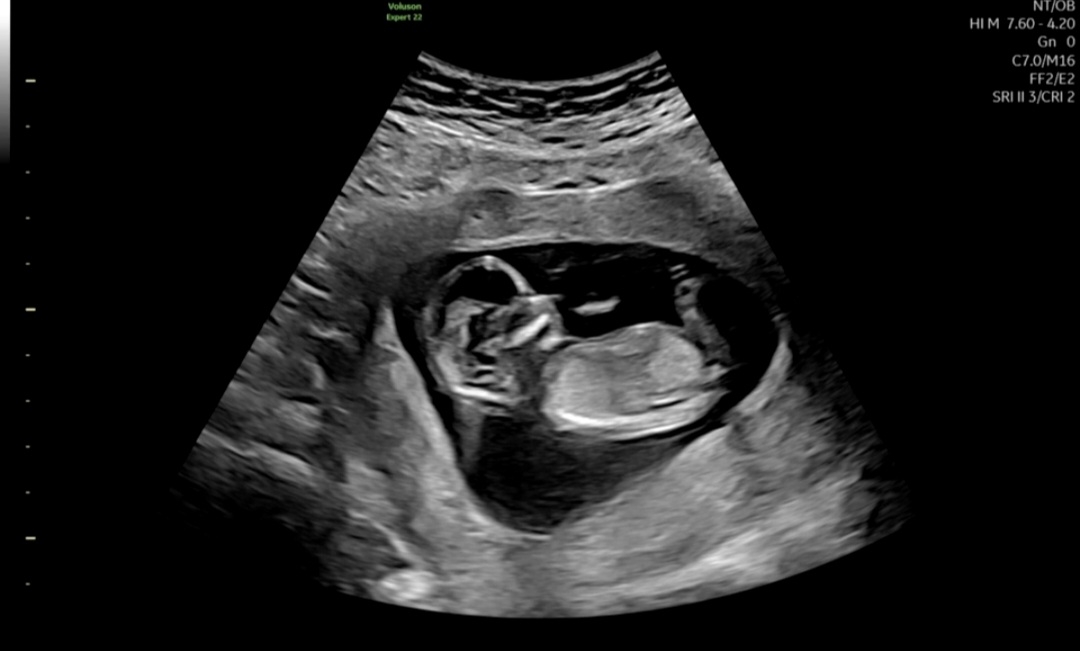

13주 각도법 잘 보시는분~~

잘안보이긴하는데ㅠㅠ혹시나..아시는 고수님 계실까용

아들같은데용?